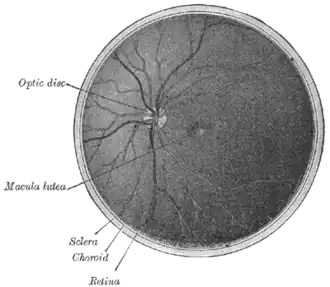

![]() Интерьер задней части глазного яблока левого глаза. Вены темнее выглядят чем артерии. | |

Диск зрительного нерва или головка зрительного нерва является зоной выхода для аксонов ганглиозных клеток сетчатки. Поскольку в этой зоне не могут располагаться фоторецепторы, то в этом месте имеется "зона нечувствительности", называемая слепое пятно. Его диаметр - примерно 5,5 угловых градусов, расстояние от "центральной ямки" (зоны наиболее плотного расположения колбочек в центре сетчатки) примерно 16 угловых градусов.

Аксоны ганглиозных клеток сетчатки образуют в месте выхода из глаза зрительный нерв, по которому сигналы от сетчатки передаются на следующие уровни обработки в зрительной системе. Обычно зрительный нерв состоит из 1-1,2 млн аксонов. Диск зрительного нерва является также точкой входа для крупных кровеносных сосудов, питающих сетчатку.[1]

Диск зрительного нерва размещён в 3 х 4 мм от носовой части ямки. Это вертикальная, овальная, со средними размерами 1.76 мм по горизонтали и 1.92 мм по вертикали.[2] Существует центральный депрессия, переменного размера, называется глазная чаша.